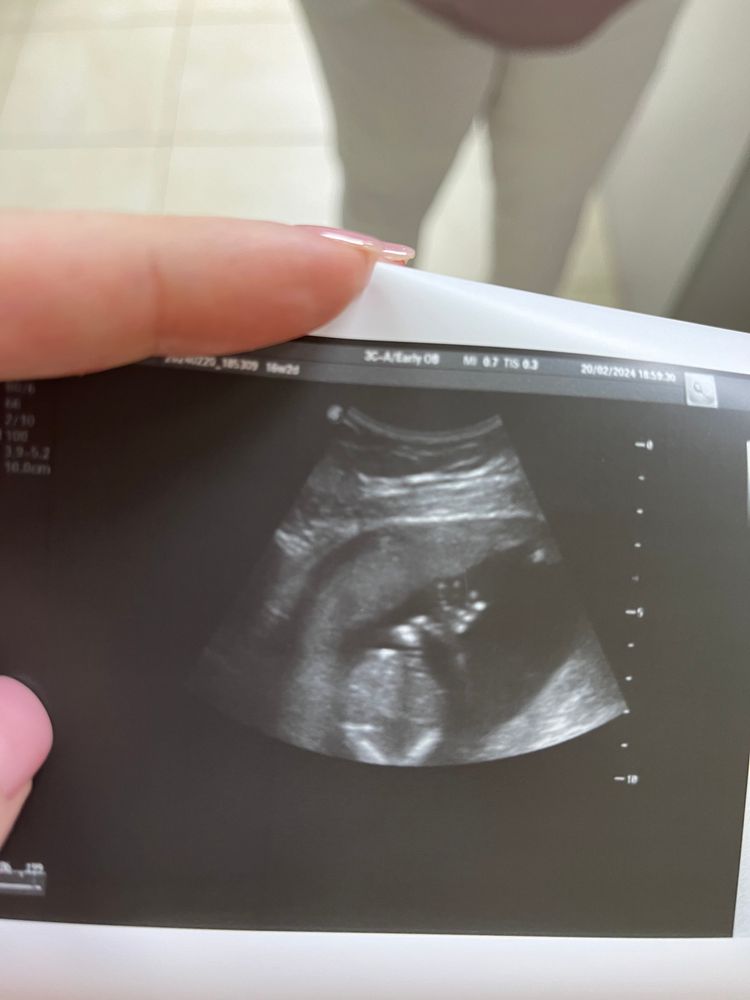

Приветик от малышки 👋🏻

Наша зайка передала привет 😇 16 недель 2 дня, по узи сказали что 80% что ждём девочку 🩷